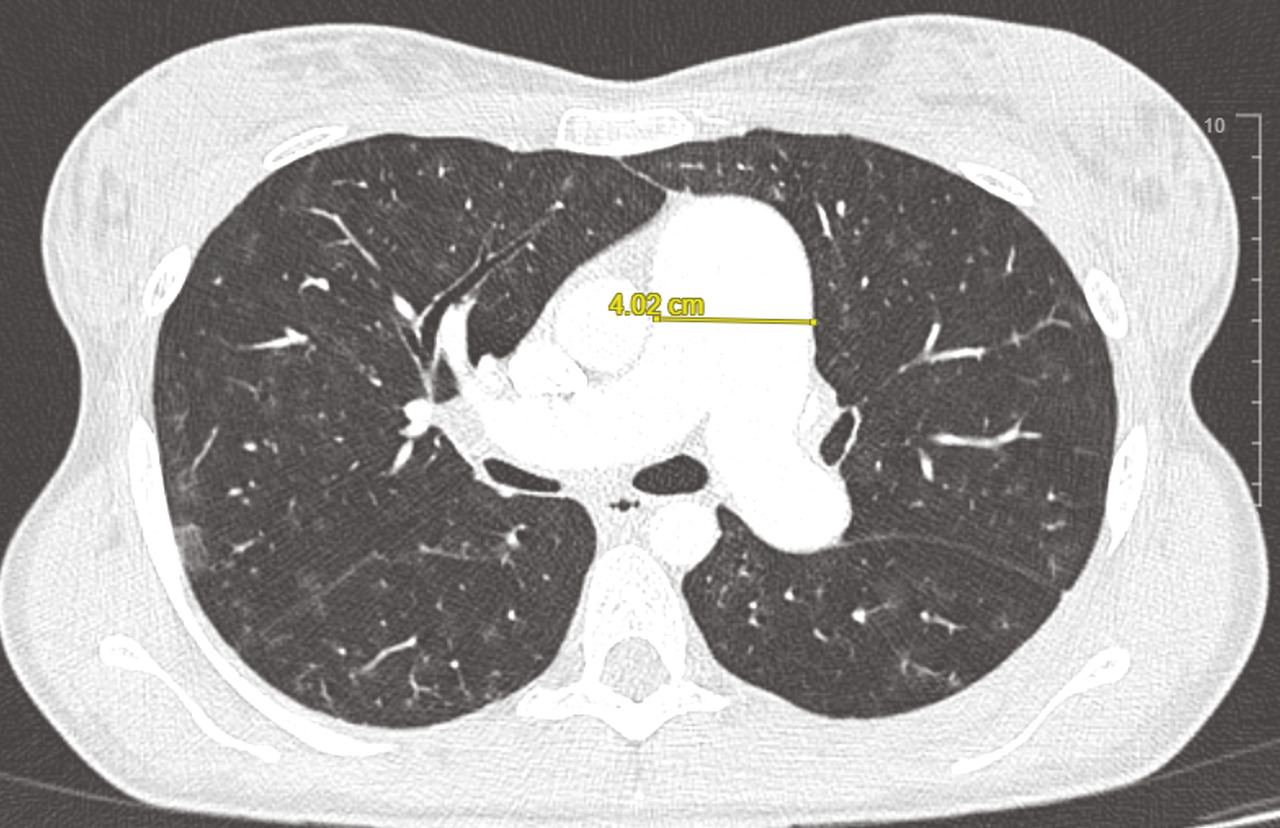

Le scanner thoracique en coupes millimétriques permet de rechercher des éléments évocateurs de maladie veino-occlusive pulmonaire (épaississement des septa, nodules flous en verre dépoli, adénopathies médiastinales) ou d’une pathologie respiratoire sous-jacente (emphysème, pneumopathie interstitielle diffuse…) [fig. 4 et 5].1,2Un angioscanner thoracique est indispensable pour le bilan d’opérabilité des patients atteints d’HTP-TEC.

L’injection de produit de contraste au temps artériel pulmonaire (angio-TDM thoracique) permet de rechercher des lésions thromboemboliques chroniques.

fig. 3 ]. Elle permet aussi de rechercher des anomalies parenchymateuses témoignant d’une maladie respiratoire associée (emphysème, fibrose pulmonaire, etc.), d’une maladie veino-occlusive ou encore d’une origine post-capillaire.1,2